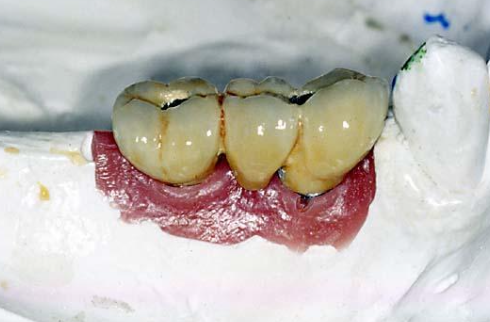

What are these?

Metal components, secured to implant using a metal threaded guide pin